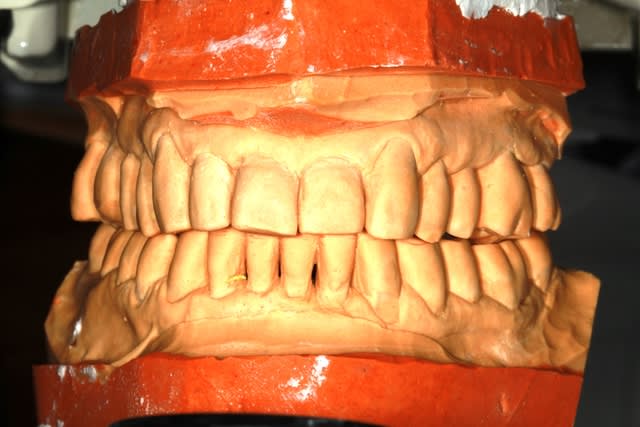

revue la patiente ce jour...avec un joli scan...rien de réjouissant.

Néanmoins, le plan de travail se met en place, et aujourd'hui, détartrage (irrigation à la betadine) constat que le terrain est miné, mais je vais quand même jouer la conservation.

Empreintes pour préparer un Waxup

les conseils sont les bienvenus, bien sur

Pourquoi conserver? parce que je crois que c'est la bonne voie

Ensuite si la situation se dégrade, il sera toujours temps de pratiquer les avulsions